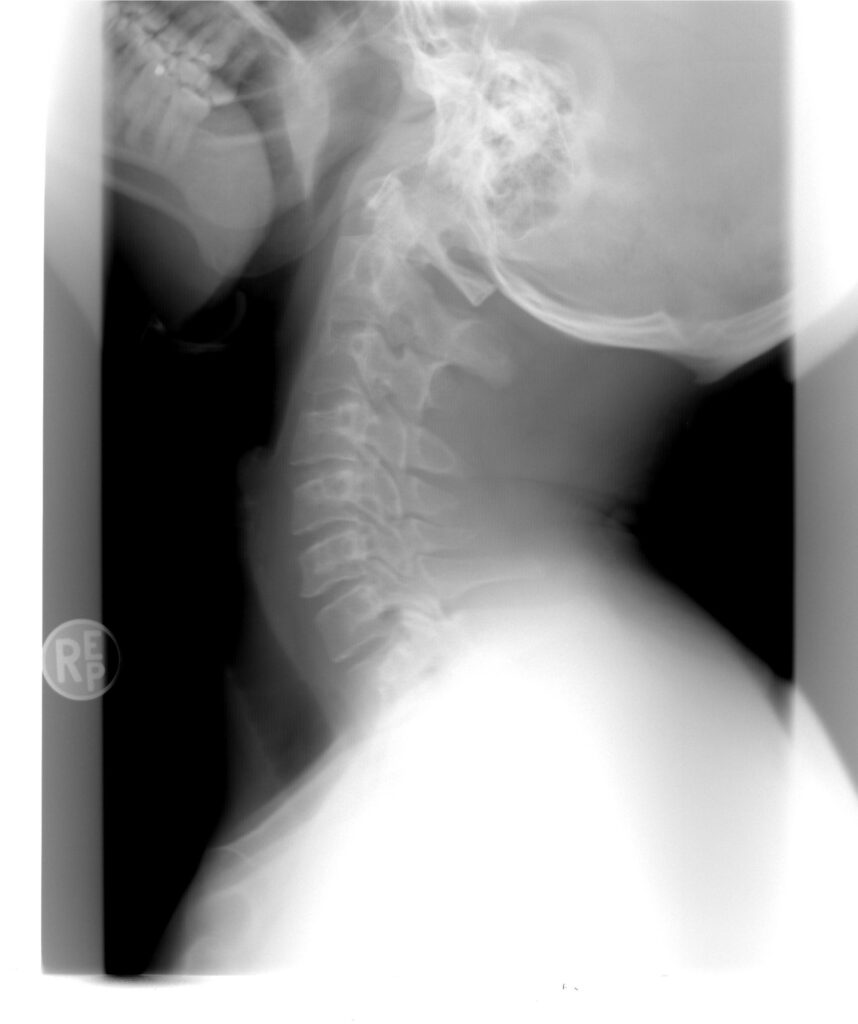

Well…here is the thing with x-rays – they only show a moment in time. Outside of serious pathology they DO NOT provide information on how to treat someone. Plus who is to say that picture of the neck didn’t look that way 6 months prior. As in when the person had NO pain or limitation whatsoever.

Here is the deal with x-rays. Anyone over the age of 40 is going to show some “change” on x-ray…it is called normal aging and has little to do with any pain or dysfunction. BUT, the moment someone knows their x-ray may look “not perfect” (again aging), they begin to worry. What might have been just a slight stiffness in the morning waking up now becomes a bigger issue. Why? Because they were told there is a “change” and that must be why they are stiff and now the brain and body start to respond negatively to relatively benign things in life.

Great question. The answer…because patients expect doctors to have an answer. And if the doctor isn’t going to perform a THOROUGH physical exam (which they have little time for), they will rely on a static picture (again which shows normal aging) and then blame anything the person feels on some “change” in the picture. That and a vast majority of patients just expect the image because they do not really know the whole truth. They do not understand that x-rays really are only good for seeking out the bad stuff (i.e. fracture, dislocations, or other bony abnormality). They do not serve to answer the question most people are really asking…why does my neck or arm hurt?